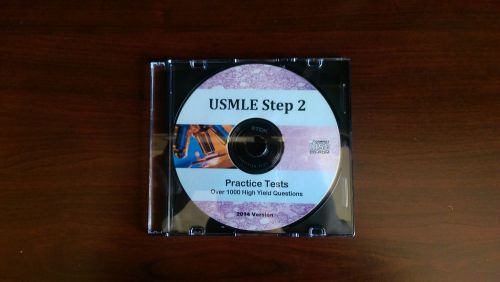

USMLE Step 2 CK Preparation Questions High Yield Qbank Practice Tests CD